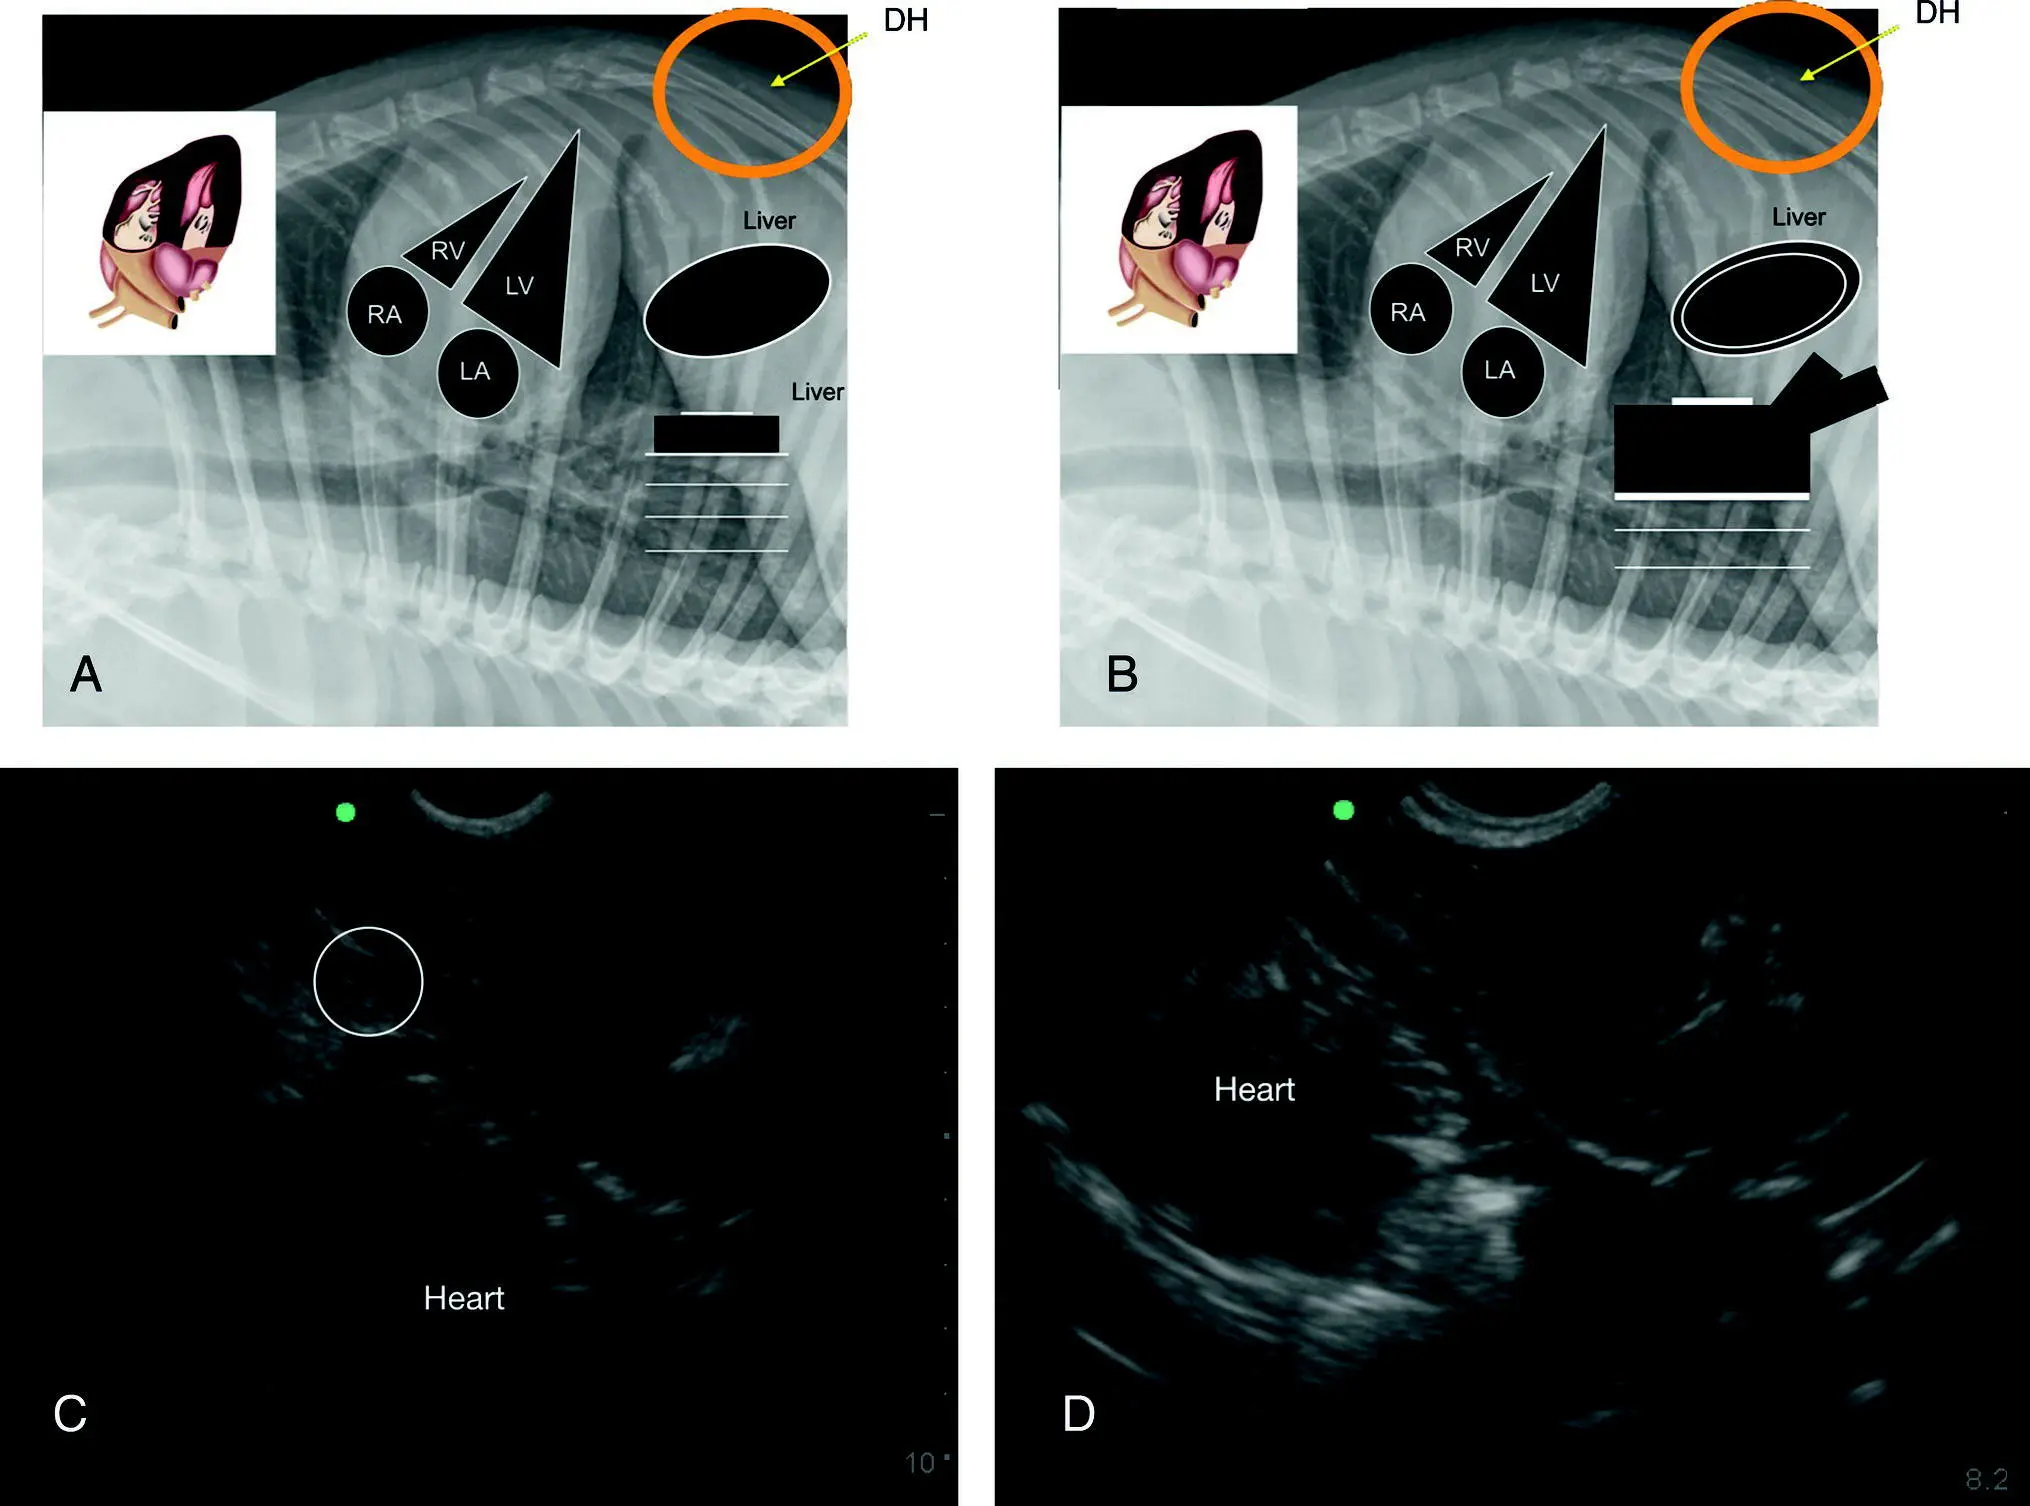

Figure 7.13. The racetrack sign of PCE with integration of the CVC characterization. (A,B) Inverted lateral thoracic radiographs to illustrate the anatomy in the ultrasound images in (C) and (D) with PCE evidenced by the rounding of anechoic fluid, referred to as the “racetrack sign” (Lisciandro 2014a,b, 2016a). Characterization of the CVC is helpful for evidence that obstructive shock and tamponade may be present. In (A) the CVC is unremarkable and in (B) the CVC is “FAT” and has associated hepatic venous distension supporting obstruction of blood flow to the right atrium. In (C) there is a small‐volume ascites ( circled ) and if a modified transudate, supports a more chronic case of PCE and a better prognosis. In (B) gallbladder wall edema, the “cardiac gallbladder,” is shown which is only expected with hepatic venous congestion and more chronicity to the PCE.

Source: Reproduced with permission of Dr Gregory Lisciandro, Hill Country Veterinary Specialists and FASTVet.com, Spicewood, TX.

Interestingly, the use of IVC distension (a “FAT” IVC) in people is only about 40% specific for the presence of cardiac tamponade. Conversely, a nondistended IVC at the subxiphoid view that has its expected normal variation in diameter in spontaneously breathing people effectively rules out cardiac tamponade with a sensitivity of 97% (Candotti and Arntfield 2015; Tchernodrinski and Arntfield 2015). The CVC in small animals likely proves similarly helpful with indirect nonechocardiographic (fallback view) information regarding the presence of obstructive shock from cardiac tamponade. We like the saying “Don't risk your patient's life trying for an echo view” – use the Global FAST fallback views (see Figure 36.7).

Pearl:Always look cranial to the diaphragm because most cases of clinically relevant pericardial effusion are detected via the DH view, which is part of AFAST, TFAST, and Vet BLUE.

Pearl:Ascites (modified transudate) in cases of PCE cases carries a better prognosis because the PCE has been a more chronic process in that patient (Johnson et al. 2004). Always stage with Global FAST and encourage pericardiocentesis when indicated in these cases.

Pearl:The nonecho option for the presence or absence of cardiac tamponade is characterization of the CVC. A “bounce” to the CVC rules out tamponade versus a “FAT” distended CVC which supports the presence of obstructive shock and cardiac tamponade and the need for emergent pericardiocentesis in weak, collapsed patients, although it's best to look at the patient to make that final decision (stable, can wait; unstable, needs emergent pericardiocentesis).